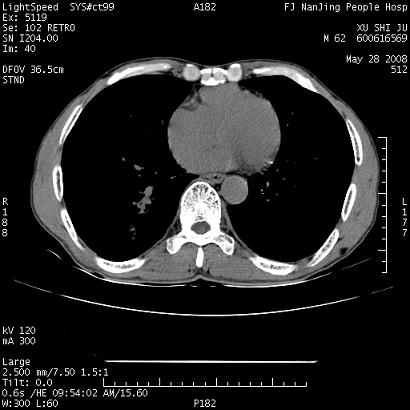

以下是引用qiushi在2008-5-28 20:01:00的发言:[br]空洞周围环状磨玻璃影(日晕征),考虑肺曲霉菌病.

以下是引用yuhongjun在2008-5-29 4:28:00的发言:[br]空洞周围环状磨玻璃影(日晕征),考虑肺曲霉菌病。支持! [br] [br]

以下是引用lrj在2008-5-28 21:10:00的发言:[br]所示应该是正常结构,是对称的,多个层面都有!也不像是内乳动脉或是肿大淋巴结![br]右下肺渗出性病变伴空洞形成,其洞内见一结节,以下诊断都有可能:1 右下肺曲菌感染, 2右下肺结核空洞形成伴曲菌感染!3右下肺结核空洞伴壁内占位形成,虽说后者发生的几率很低 但作为我们应该多考虑一下吧!最重要的结合临床